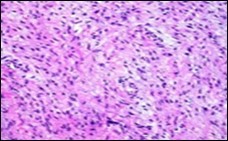

The neoplasm frequently infiltrates abutting skeletal muscle. Occasionally, tumefaction denominates hyper-cellular foci, tumour necrosis, cellular or nuclear atypia and mitotic figures, features which are characteristic of intermediate to high grade sarcoma. Localized tumour reoccurrence may be hyper-cellular with enhanced mitotic activity 4, 5. On ultrastructural examination, fibroblastic differentiation is exemplified 5. Figure 1, Figure 2, Figure 3, Figure 4, Figure 5, Figure 6, Figure 7, Figure 8.

Figure 2.Low grade fibromyxoid sarcoma exemplifying intermingled foci of fibrous and myxoid regions of spindle-shaped cells with minimal pleomorphism and absence of mitosis (10).